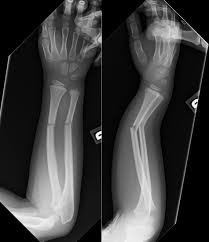

手首の骨折で気をつけること!

手首の骨折の合併症

手首を骨折したときは、骨折単独ではなく靭帯や腱を巻き込んで起こることがあります。

また外傷をともなう複雑骨折や開放骨折の場合は、感染症などの合併症を起こすこともあります。

完全に折れた完全骨折ではなく、ヒビなどの不完全骨折の場合は、腱鞘炎や捻挫と勘違いして処置が遅れたり、気づかないまま固まったりすることがあります。